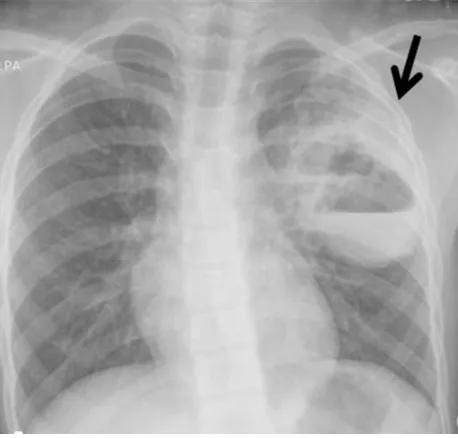

61세 남성이 지난 10일 동안 지속된 발열과 함께 불쾌한 냄새가 나는 화농성 객담을 호소하며 병원을 찾았다. 환자는 15년간 흡연한 이력이 있으며, 최근 3년 간 매일 소주 두 병을 섭취하는 등의 과음 습관이 있었다. 또한, 환자는 몇 주 전에 치주 질환으로 치과 치료를 받았다고 한다. 아래는 환자의 흉부 X선 사진 결과이다. 이 환자에게 가장 적절한 치료 방법은 무엇인가?

알콜중독과 치주염 병력으로, 혐기균의 aspiration risk 높은 환자다. 가슴 X선에서 air-fluid level이 보이는 thick walled cavity가 보이므로 lung abscess를 의심할 수 있다. 또한 불쾌한 냄새의 화농성 객담은 "Putrid lung abscess"를 시사하는 소견이다.